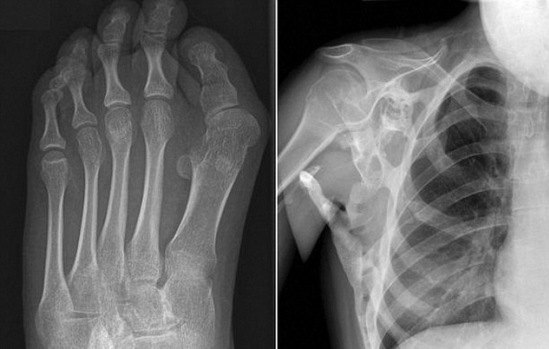

Ezt a kegyetlen kórt FOP-betegségként hívják, és a lánynál 12 éves korában fedezték fel, mikor egy iskolai sportesemény után sérülés miatt orvoshoz kellett vinni. A tini a gerincét fájlalta, ahol egy hatalmas vörös daganat képződött, amely forró volt és fájdalmat okozott neki. Ekkor vizsgálták meg alaposabban az orvosok és jöttek rá a szindrómára.

Sajnos az FOP miatt Seanie izmai és inai csonttá változnak, és kerülnie kell minden sérülést, ütést, gyulladást, mert újabb csontnövekedéshez vezethet. Akár még egy injekciótól is komoly baja lehet a lánynak, bár ahogy egyre rosszabb lesz az állapota kevésbé tudja megőrizni az egyensúlyát.

Annak ellenére, hogy a fiatal lány még csak 17 éves a karjait már képtelen kinyújtani, mert a könyökízületei már csonttá váltak, így behajlítva rögzültek a végtagjai. Nem szabad elesnie, mert nem tudja védeni magát az ütésektől. Emellett a csontosodás a vállaiban is elindult és ezért a karjait felfelé alig képes mozdítani. Így nagy erőfeszítés árán tud csak fogat és hajat mosni. Sőt most már az öltözésben is a családtagjai segítségére szorul, akik mindent megtesznek, hogy megkönnyítsék az életét Seanienak.